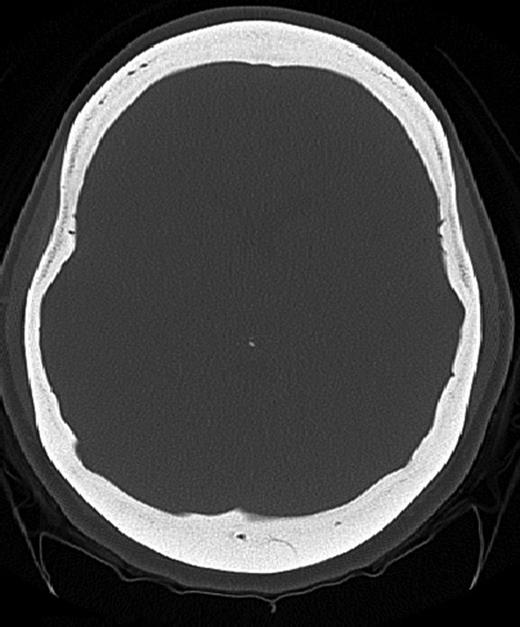

A 25-year-old female patient presented with 1-year history of occipital headache. The headache was increasing with coughing, sneezing and bending over. She had also complaints of intermittent bilateral hand numbness and bilateral feet burning. She was evaluated with magnetic resonance imaging (MRI), which showed Chiari I malformation with a 7 mm descent of cerebellar tonsils (Fig. 1 a and b). Computed tomography demonstrated diffuse calvarial thickening and loss of the medullary space (Fig. 2). Her past medical history was consistent with left eye surgery due to amblyopia when she was a child and she was blind in her left eye. Radioactive 131I treatment had been given due to the Graves’ disease and hyperthyroidism; therefore, she was hypothyroidic and was using levothyroxine daily. Her mother also was operated on because of the Chiari malformation. She had four siblings, and they did not have any pertinent medical history. Her physical examination revealed prominent occipital area and midfacial hypoplasia. Increased cortical thickness in her long bones was also demonstrated (Fig. 3 a–c). There were no abnormal findings on neurological examination except of left eye amorozis. The patient underwent surgery for decompression of posterior fossa. Large enough posterior fossa craniectomy with C1 laminectomy was performed with SSEP and MEP monitoring. Dura was opened in ‘Y’ shape, and duraplasty was performed with the pericranium. Arachnoid was kept intact. Her headaches improved significantly in postoperative period. She developed superficial wound infection, which was treated with simple washout and antibiotics.

Patients' picture showing midfacial hypoplasia on the face (a), x-ray graphy of the right femur (b) and x-ray of left femur (c) showing diffuse cortical thickening.